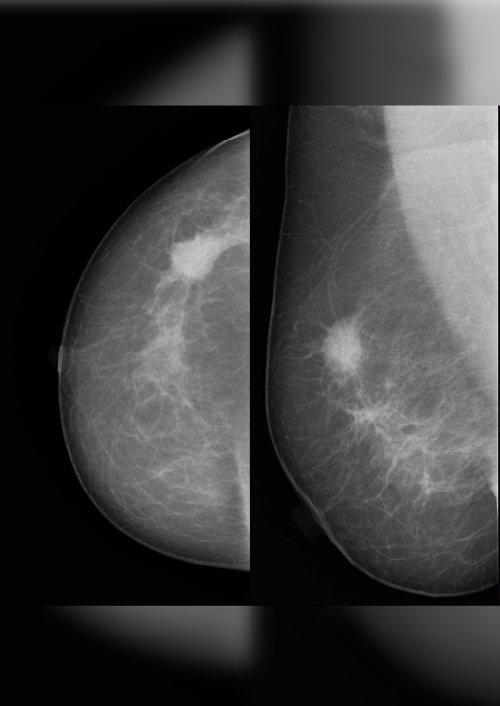

Es prevenir, detectar y tratar a tiempo el cáncer ginecológico y de mama, con un enfoque integral, humano y basado en evidencia. Este espacio fue creado para ayudarte a entender tu cuerpo, resolver tus dudas y priorizar la prevención como una herramienta clave para tu salud y calidad de vida.

Tu bienestar merece una mirada experta. Te ofrezco atención ginecológica integral junto con una prevención oncológica avanzada en cada paso de tu camino.